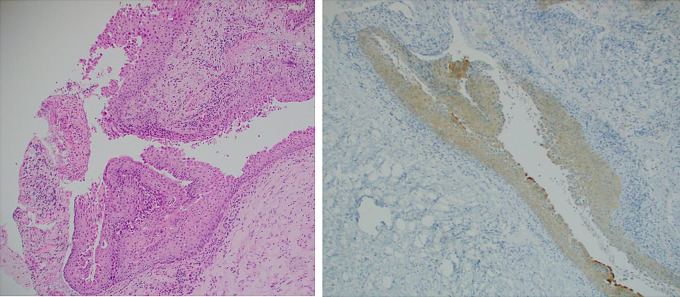

Results: Of eleven patients with suitable operative specimens, one patient with an initial diagnosis of RCC was revised to pCP following BRAF testing with equivocal positivity on BRAF IHC and clear identification of the V600E variant on NGS. The patient's subsequent clinical course was aggressive and more compatible with pCP than RCC.

Conclusion: This study highlights the potential value of BRAF testing in RCCs to identify missed pCP, which is an especially timely finding given the advent of primary medical therapy with BRAF inhibition for pCP. In the absence of guidelines advising on the use of BRAF studies in sellar lesions, we suggest consideration of BRAF testing of all RCCs, particularly if there is squamous metaplasia or disease recurrence.